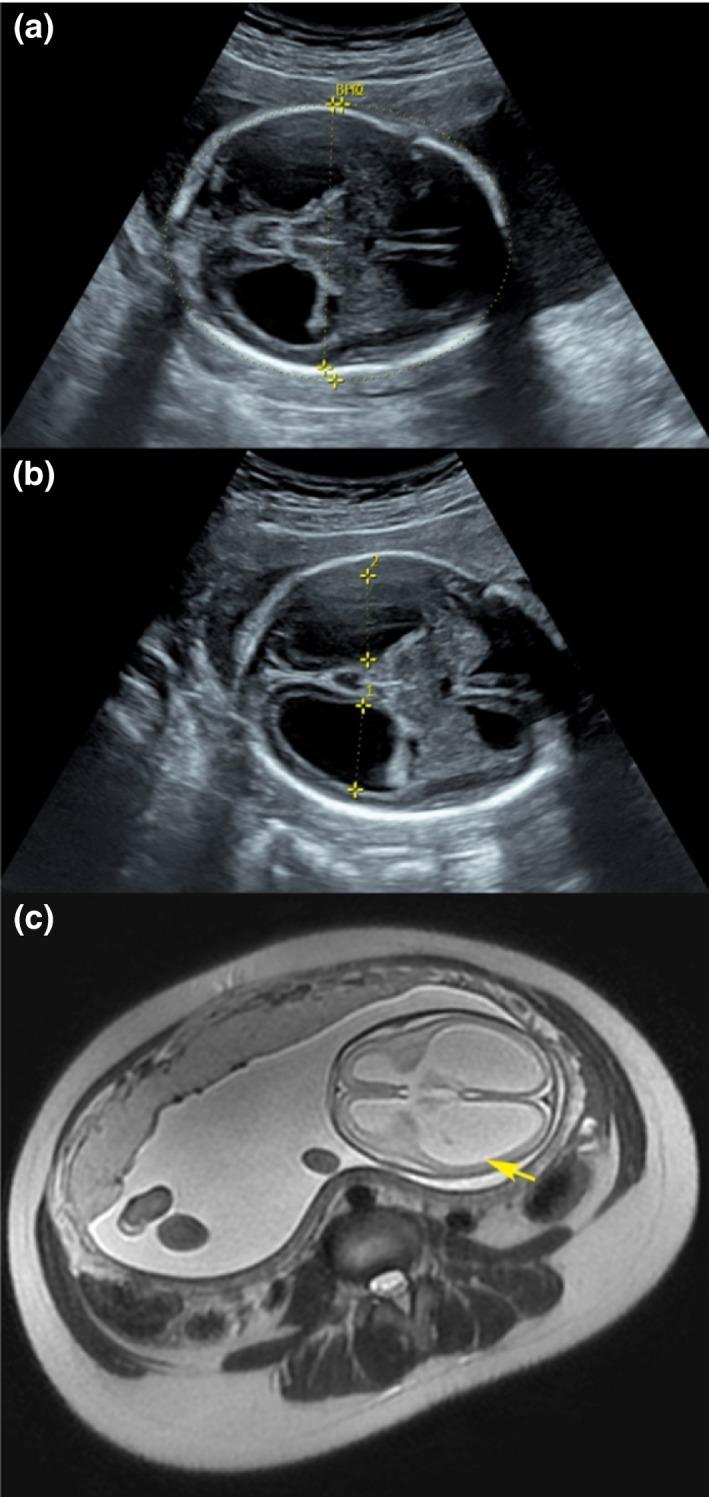

X-linked hydrocephalus (XLH), characterized by mental retardation and bilateral adducted thumbs, often come out to be a genetic disorder of L1CAM. It codes the protein L1 cell adhesion molecule (L1CAM), playing a crucial role in the development of the nervous system. The objective of the study was to report a new disease-causing mutation site of L1CAM, and gain further insight into the pathophysiology of hydrocephalus.

The variant c.2491delG (p.V831fs), located in the exon 19 of L1CAM (chrX:153131214), could damage the L1CAM function by producing a frameshift in the translation of fibronectin type-III of L1CAM.

X 连锁脑积水(XLH)的特征为智力迟钝和双侧内收拇指,通常是 L1CAM 的遗传疾病。它编码 L1 细胞黏附分子(L1CAM),在神经系统发育中起着关键作用。本研究的目的是报告 L1CAM 的一个新致病突变位点,并进一步了解脑积水的病理生理学。

位于 L1CAM 外显子 19 中的 c.2491delG(p.V831fs)变异(chrX:153131214)可通过 L1CAM 纤连蛋白 III 翻译产生移码而破坏 L1CAM 功能。